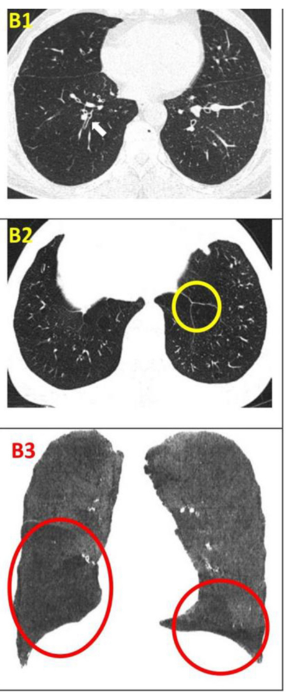

影像學(xué)檢查改善:CT 值在 - 1000 至 - 951 比例有所下降,Class4( % ) 亦明顯下降,故肺氣腫較治療前好轉(zhuǎn)。附圖為雙源 CT 肺實質(zhì)分析軟件,深藍(lán)色表示 CT 值在 -1000 至 - 951,治療后較治療前深藍(lán)色面積明顯縮小。

干細(xì)胞移植前后的肺部CT檢查對比

結(jié)論:干細(xì)胞治療前與治療后多次評估對比生活質(zhì)量評分及傳統(tǒng)肺功能檢查指標(biāo),隨訪6個月左右,結(jié)果提示短期內(nèi)生活質(zhì)量評分及傳統(tǒng)肺功能檢查改善程度小,而應(yīng)用肺部雙源 CT 定性及 CT 值定量分析肺功能提示治療后肺氣腫明顯好轉(zhuǎn),未出現(xiàn)嚴(yán)重不良事件。可以達(dá)到干細(xì)胞治療慢阻肺短期療效的目標(biāo)。